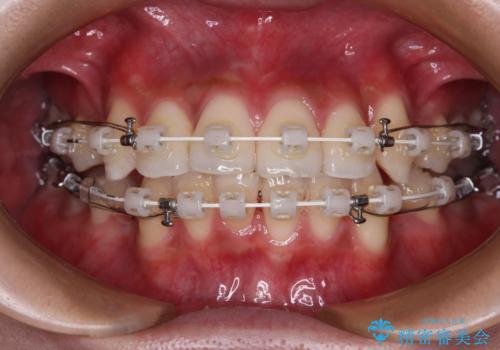

- 矯正装置

- 審美装置

- 八重歯と口元の閉じにくさを気にして来院された患者様です。

非抜歯矯正で歯列を整えると、治療後に口元が今よりも突出する可能性が高かったため、上下左右の第一小臼歯4本を抜歯し、ワイヤー装置にて矯正治療を行うこととしました。

患者様の望んでいた通りの歯列や口元に仕上げることができました。